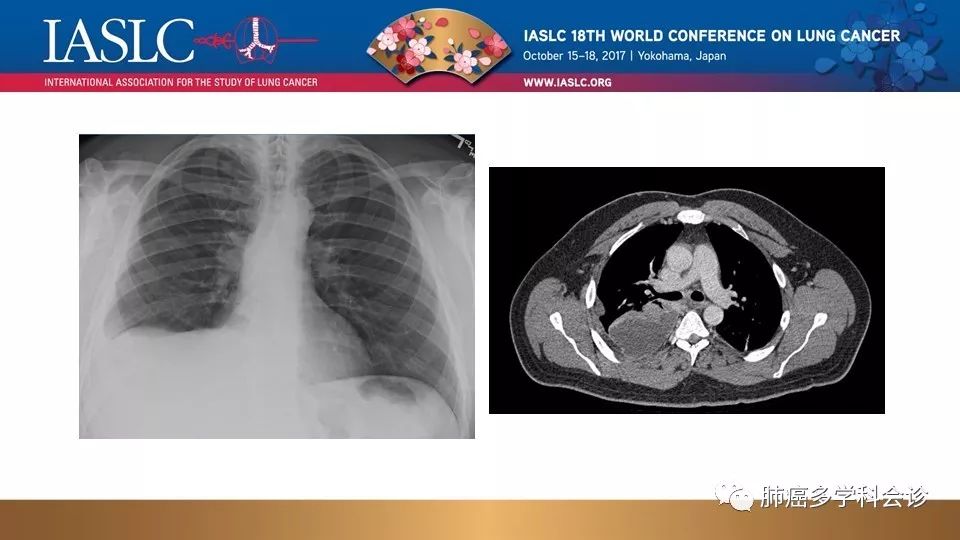

ALK重排的非小细胞肺癌治疗(附病例)